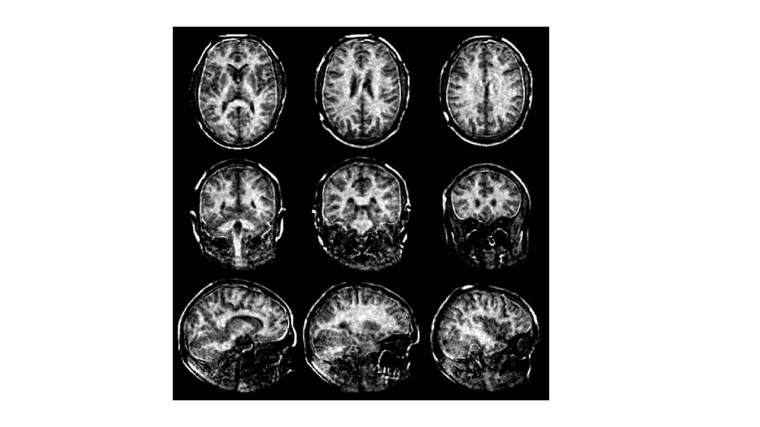

Multiple Sklerose mit neuem MRT-Verfahren sichtbar machen

ETH-Forschende haben ein neues Verfahren der Magnetresonanztomographie (MRT) entwickelt mit dem Multiple Sklerose (MS) frühzeitig erkannt und besser überwacht werden kann.

Das Verfahren bildet die Myelinscheiden im Gehirn genauer als bisher möglich ab. Der Verlust der Myelinscheiden ist ein wichtiges Merkmal der Multiplen Sklerose. Das neue MRT-Verfahren mit speziellem Kopfscanner könnte Forschenden auch dazu dienen, weitere feste Gewebetypen wie Bindegewebe, Sehnen und Bänder besser sichtbar machen.

Das neue MRT-Verfahren der ETH-Forschenden löst dieses Problem und misst den Myelingehalt direkt. Es versieht die MRT-Aufnahmen des Gehirns mit Zahlenwerten. Diese zeigen, wie viel Myelin an einer bestimmten Stelle im Vergleich zu anderen Bereichen des Bildes vorhanden ist. So bedeutet die Zahl 8, dass der Myelingehalt an dieser Stelle nur 8 Prozent von einem Maximalwert von 100 beträgt, was auf eine deutliche Ausdünnung der Myelinscheiden hinweist. Grundsätzlich gilt: Je dunkler der Bereich und je kleiner die Zahl im Bild, desto stärker sind die Myelinscheiden reduziert. Mit diesen Angaben könnten Ärzte den Schweregrad und Verlauf von MS besser einschätzen.